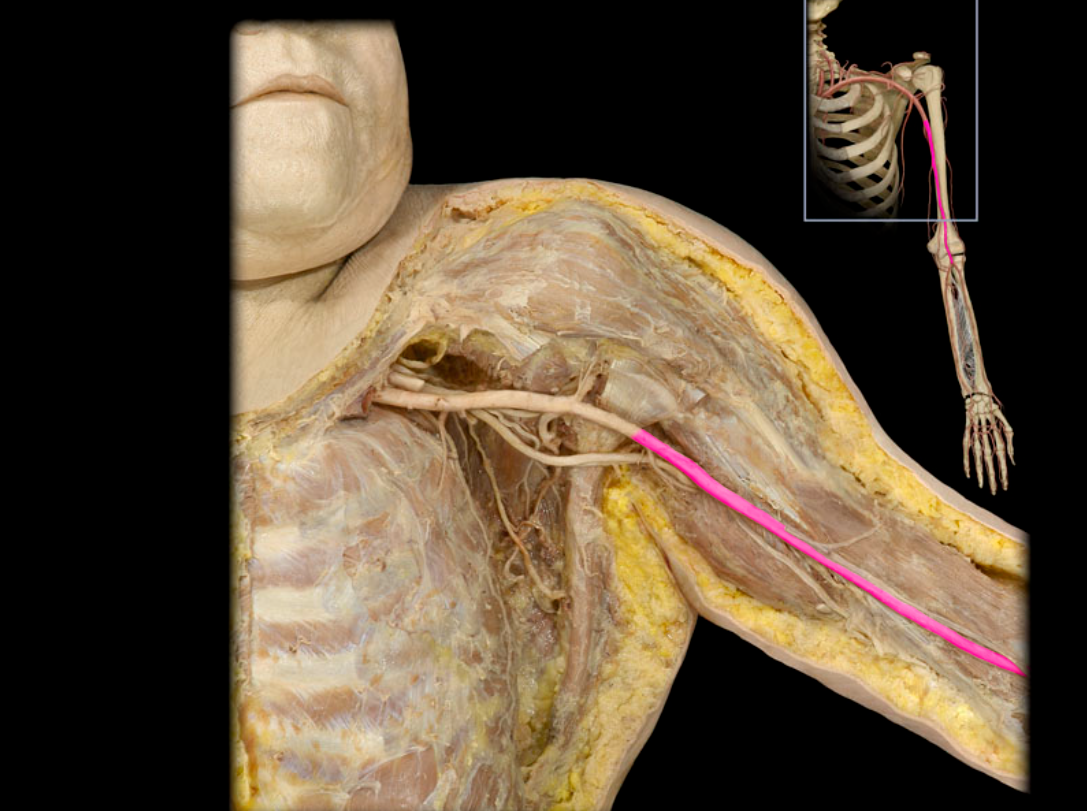

Axillary a.

Brachial a.

Subclavian v.